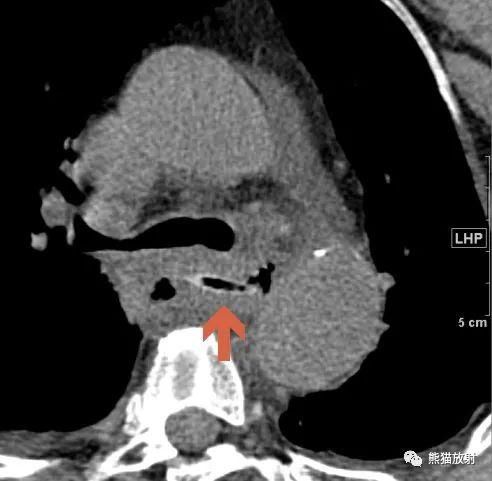

2020年5月据信息时报报道,广东的梁先生喝酒后开始大口吃鱼,一根鱼刺卡在食管,但因饮酒后神经反射的迟滞,误吞鱼刺的他浑然不知。结果刺破了食管,突破了纵膈,并插入了第六胸椎附近的主动脉里,形成了大小约4cm×5cm假性动脉瘤,随时有生命危险。经过中山大学附属第一医院心脏外科、胸外科、内镜室、影像科、B超室、麻醉科等十多个学科团队的协力合作才保住了性命,堪称九死一生。

文章图片

从患者体内取出的鱼骨,长约2.5cm